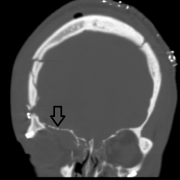

- Accurately identify fractures using CT and 3DCT radiographic findings to prescribe the appropriate treatment required for midface and zygoma fractures.